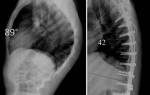

Для стабилизации деформированных позвоночных сегментов проводится операция, во время которой на позвоночный столб крепятся титановые пластины или другие металлоконструкции.

При наличии данных патологических состояний проводится операция, на позвоночнике вставлены болты, делающие поврежденные сегменты неподвижными.

- Транспедикулярная стабилизация. С помощью специальной ножки (педикулы) в смежные позвоночные тела вставляется корригирующая металлическая конструкция в виде винтов, крепко соединенных между собой штангами. Подобная техника чаще всего применяется при смещении или переломе позвонков.